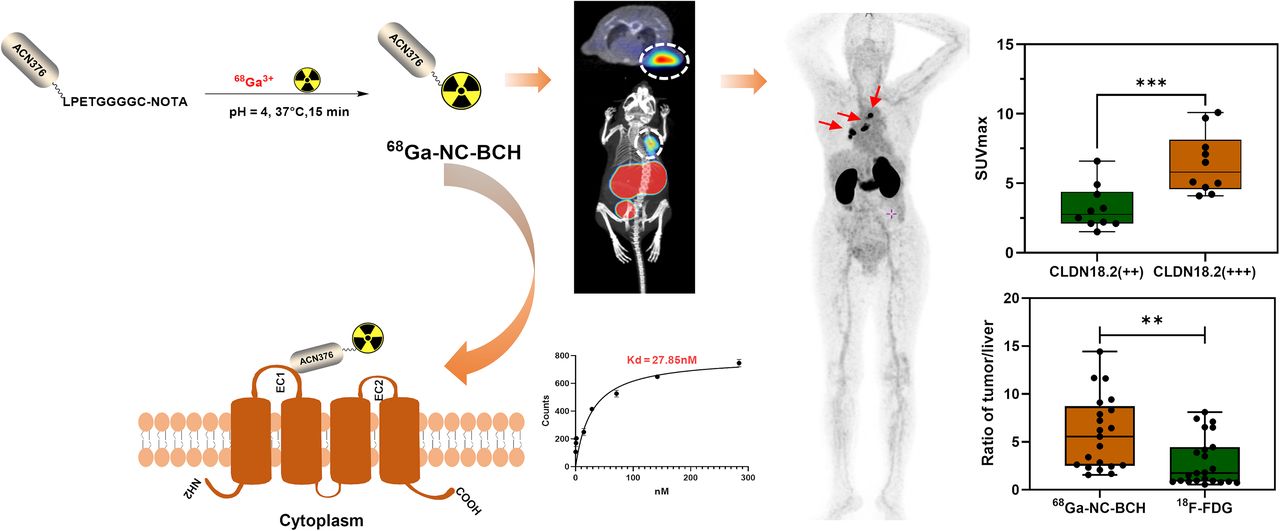

PET Imaging in Clinical Oncology | SpringerLink。Technology Focus – Diagnostic PET/CT Scan at Summit Cancer。What Does PET Imaging Bring to Neuro-Oncology in 2022? A Review。PETによるがん診断の専門書で、詳細な技術情報を提供。BLS 一次救命処置 AHAガイドライン2020準拠 プロバイダーマニュアル。。PET Scans Can Spare Lymphoma Patients Intensive Chemo。- タイトル: PET in Clinical Oncology- 著者: Helmut J. Wieler, R. Edward Coleman- ISBN: 978-3-7985-1219-1- 出版社: Springer- 言語: 英語- 内容: PETによるがんの診断と治療に関する詳細な情報を提供する専門書。ご覧いただきありがとうございます。医学生・研修医のための神経内科学